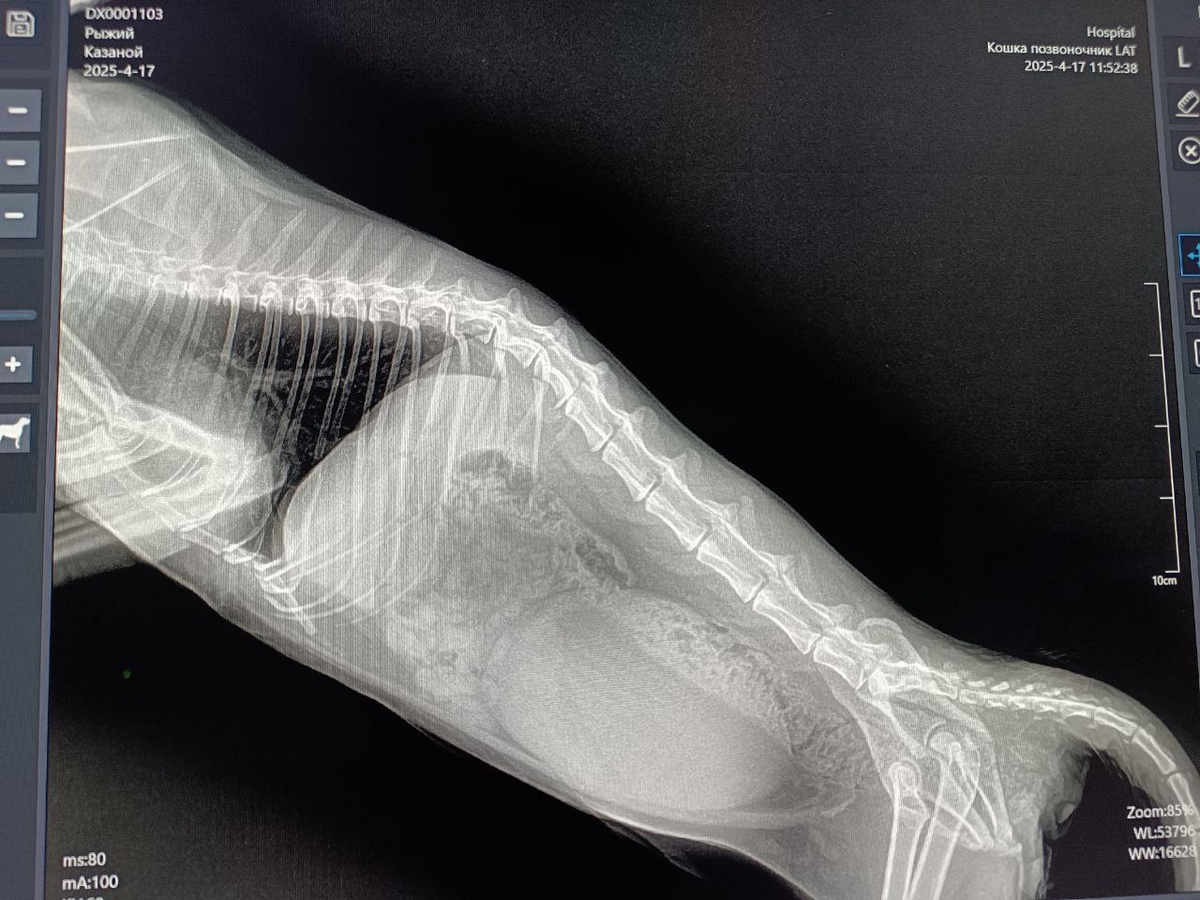

Теперь о главном, о нашем новом мальчишке Рыжике. Диагноз , как приговор, передвигаться на своих лапках он больше не сможет никогда.Перелом позвоночника в пяти местах и сложный перелом тазобедренных костей.Сейчас осложнен тем , что сильно воспалены гениталии, проблемно сцедить мочевой.Есть небольшая газация лёгких , но это результат удара. Я понимала, что услышу примерно такой диагноз и конечно же уже про себя знала , что ходить он не будет.Ну так , как говориться грустить некогда, работаем!Солнце высоко!